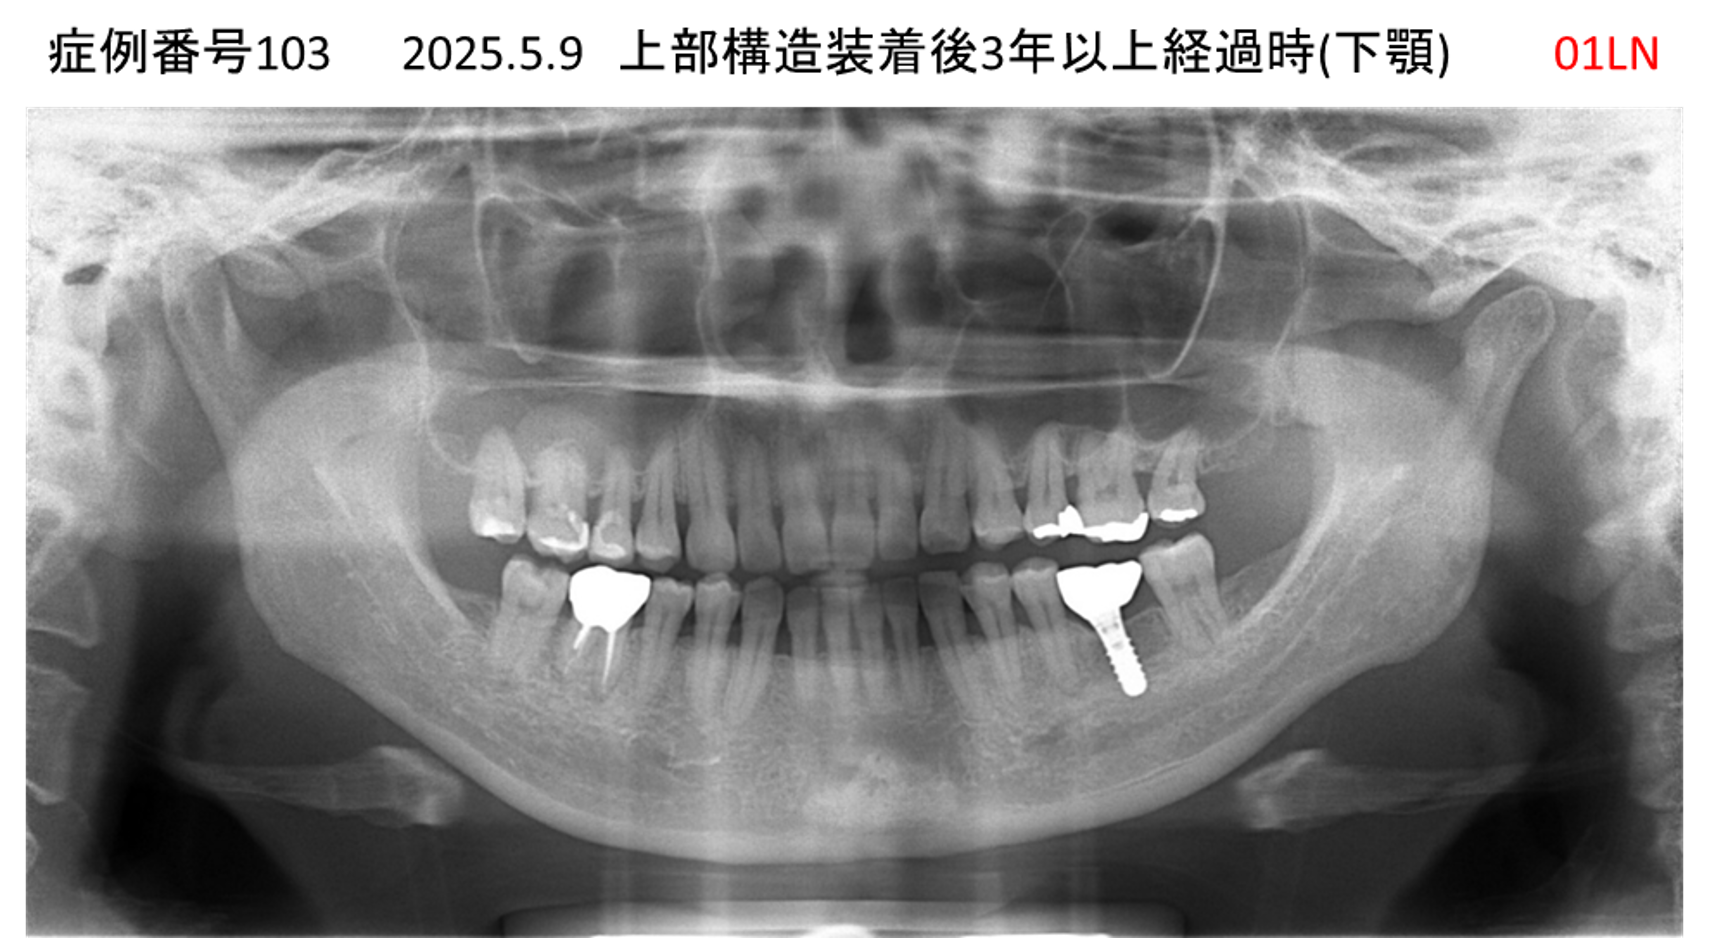

奥歯で噛めない患者様のインプラント症例

| 治療名称 |

インプラント |

| 治療費用 |

150万円+税 |

| 治療期間 |

3か月 |

| 患者さんの症状(主訴) |

奥歯で噛めない。食事がとれない。 |

| 治療内容 |

| 治療結果 |

食事に困らない。何でも食べられる。 |

| 治療の注意点(リスク/副作用) |

インプラントが壊れたら再治療が必要 |